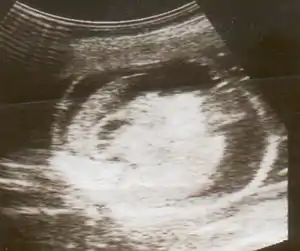

Hidropisia fetal pode ser diagnosticada e monitorada por ultrassom. O exame Pré-natal e a ultrassonografia permitem a identificação precoce de hidropisia fetal.